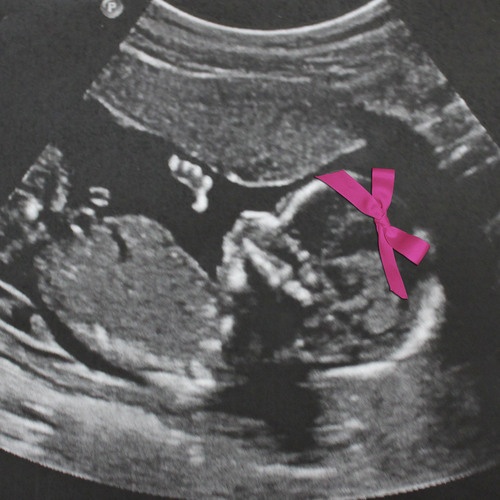

YEP! We’re adding a girly vibe to our tribe! IT’S A GIRL!!!!!!!!!

The boys are excited, we’re SUPER excited, and now it’s on to the name game. We thought for sure boy, and so we have no idea what to name this sweet little fairy child! We’ll keep ya updated. Woo hoo!!!!

And I just thought this was the cutest idea! (although not our baby girl in the pic because she didn’t like her profile shot taken haha)